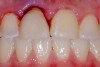

Plugging into digital workflows provides opportunities to integrate CAD/CAM technologies at every step of the treatment process for dental implants. In another example, a patient presented with a failing tooth No. 8 (Figure 6 and Figure 7). After discussing treatment options, the patient chose to forgo any treatment to address tooth and soft-tissue asymmetries and wanted to proceed with a dental implant-supported restoration without additional treatment. After integrated 3-dimensional planning, the tooth was extracted, and then an implant and the final custom CAD/CAM abutment (titanium base with zirconia supra-structure) were placed with a provisional restoration in the same visit (Figure 8 and Figure 9). Soft-tissue grafting was also done at the same visit to address the deficient buccal tissue height on No. 8 (Figure 10). At 3 months, the patient presented for the final restoration, with excellent healing around the implant (Figure 11) and soft-tissue healing guided by the custom abutment (Figure 12).

Fig 6. Clinical presentation of patient with a failing tooth No. 8.

Figure 6

Fig 7. Preoperative radiograph showing previous endodontic therapy on tooth No. 8.

Figure 7